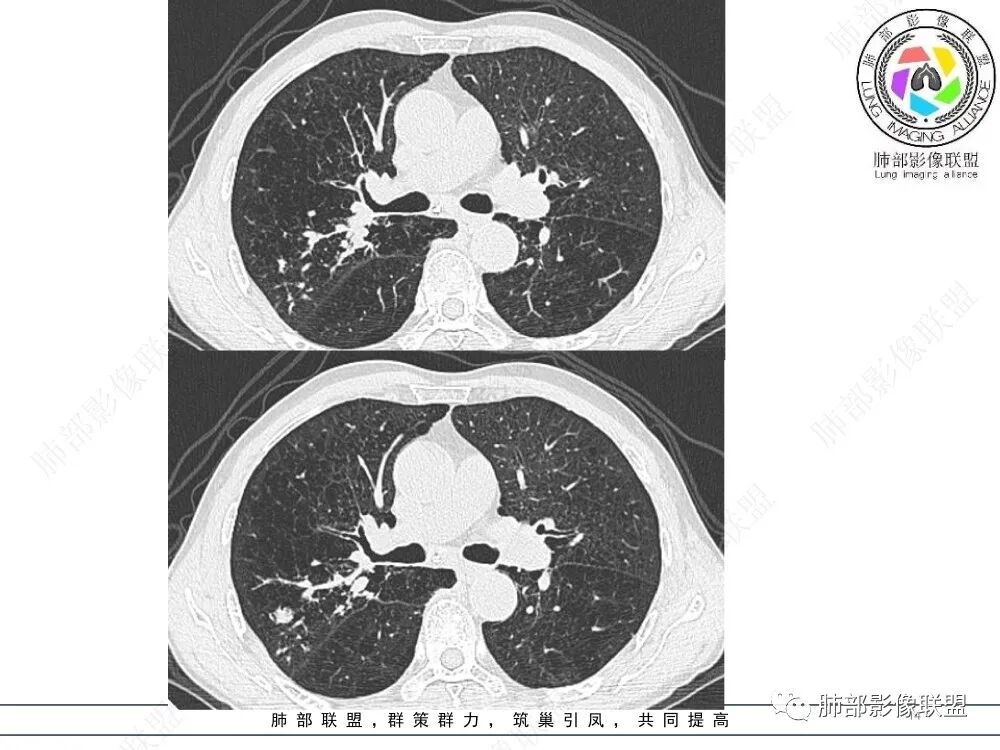

上图,鳞癌,腔内软组织占位,局部膨大,不均匀强化,伴远端粘液栓。

上图,小细胞肺癌,病灶从肺门朝外沿支气管爬行,呈指套样改变,病灶周围阻塞性肺炎较轻。

上图,粘液表皮样癌,支气管腔内病灶轻中度强化。

上图,类癌,支气管腔内占位,强化明显,远端粘液栓。